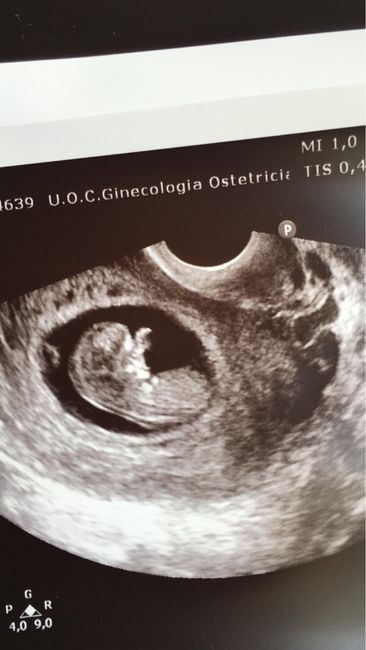

Eccola/o

Da Giulia , Il 10 Settembre 2016 alle 14:27

Buongiorno a tutte! Sono appena rientrata da una visita di controllo dati che mercoledì prossimo faró il prenatal safe, è tutto ok e sono felicissima! Per il sesso è...